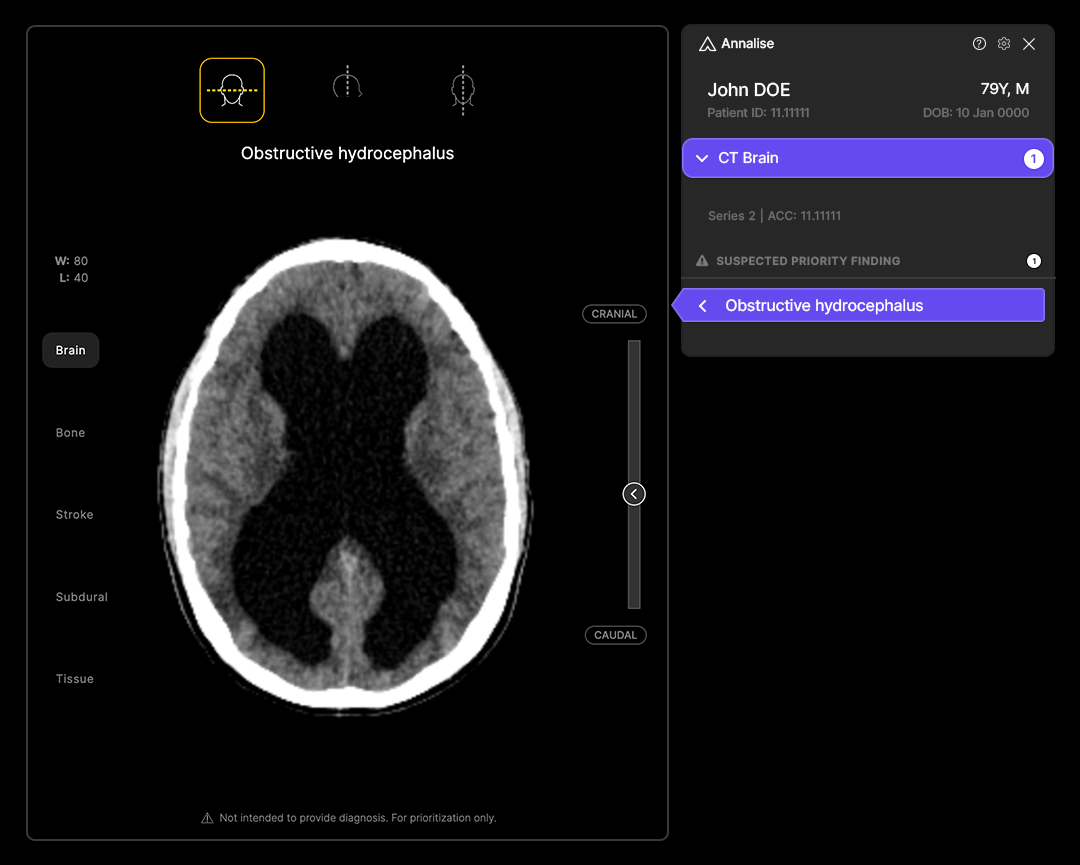

Indicated for the triage and notification of obstructive hydrocephalus on non-contrast brain computed tomography (CT), the artificial intelligence (AI)-enabled software is reportedly the first radiology triage modality to obtain the Food and Drug Administration’s (FDA) Breakthrough Device Designation.